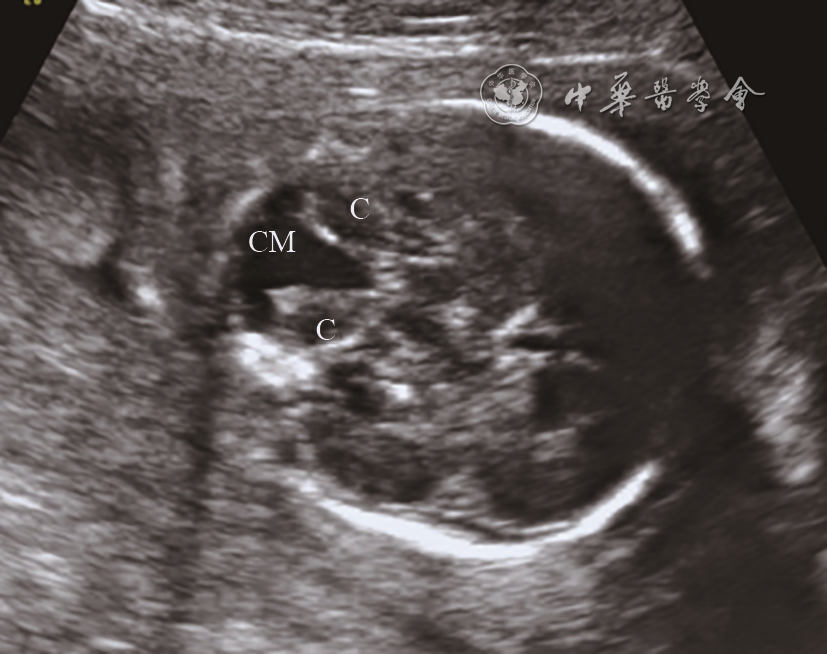

图3 胎儿Dandy-Walker畸形超声声像图(孕23+6周)。经小脑横切面:无小脑蚓部,小脑延髓池与第四脑室相通,小脑半球呈“八”字形分离

注:CM为小脑延髓池,C为小脑半球

Dandy-Walker畸形超声表现为小脑蚓部显著发育不良或缺失,小脑半球分离,小脑延髓池显著扩张并与第四脑室相通,声像图改变显著,其表现在中孕筛查期即较为明显,不易漏误诊。Dandy-Walker畸形常合并多种颅内外畸形7,预后差,本组中4例Dandy-Walker畸形均合并其他颅内外异常,中孕早中期均已正确诊断。小脑发育不良表现为小脑半球体积小,使小脑延髓池增宽,可为单纯性或与染色体异常和其他结构异常相关,出生后有中-重度神经系统发育迟缓8。超声检查通过小脑形态观察和小脑横径测量即可诊断,不易漏误诊。